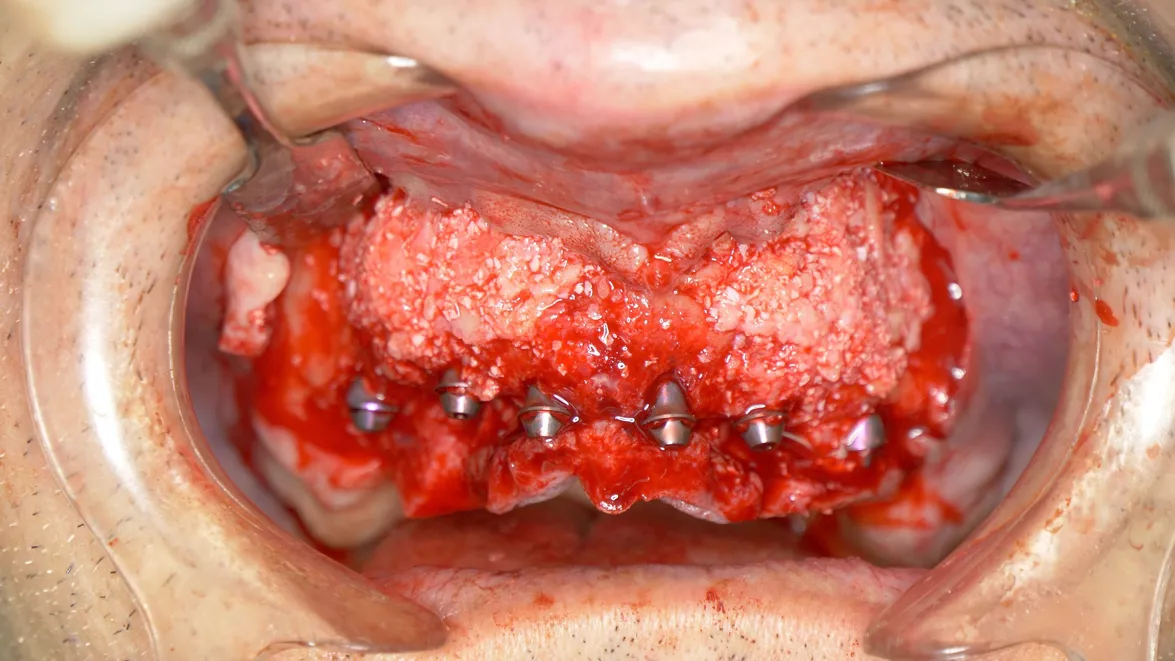

Immediate full-arch rehabilitation with Straumann® Pro Arch BLX (courtesy of J. Caramês)

• Immediate full-arch rehabilitation in the soft bone using Straumann® BLX 3,75 mm from 6 mm till 12 mm in one case (courtesy of B. Sobczak).

• Immediate full-arch rehabilitation using Straumann® BLX 3.75 mm implant in the soft bone (courtesy of L. Cuadrado).